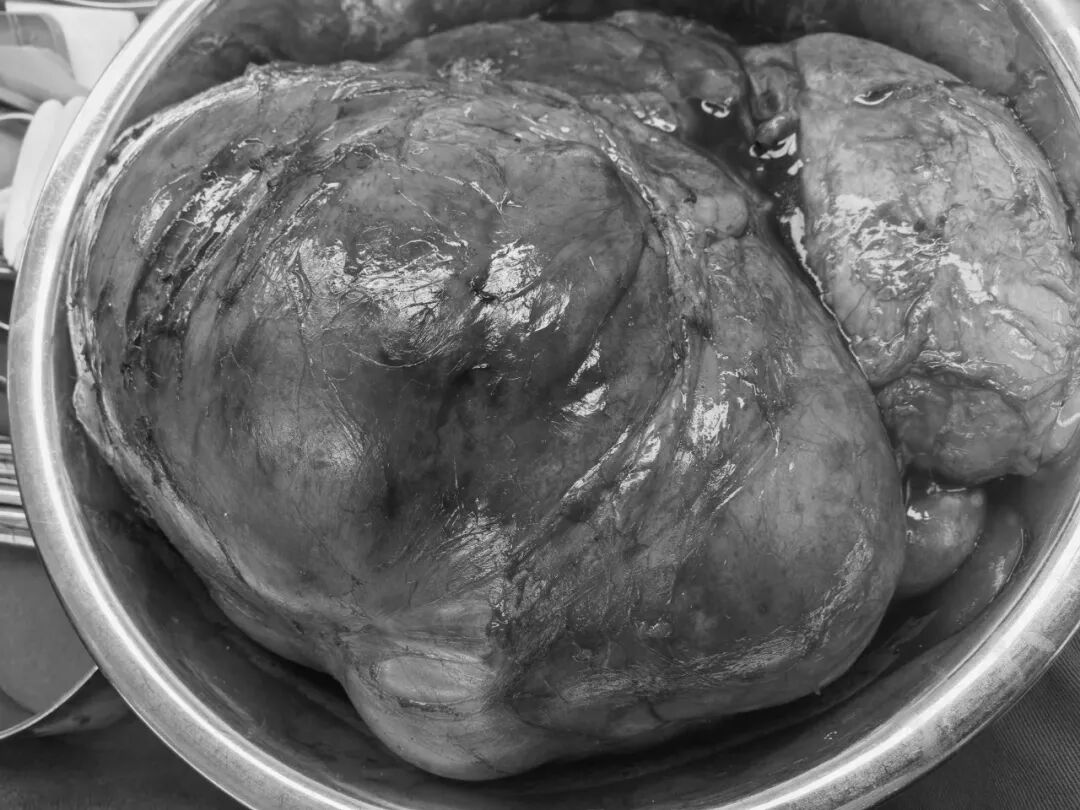

手术当天,在韩聪祥副院长的带领下,泌尿二科团队与普外二科邹耀祥主任紧密协作,手术按既定方案有序推进。术中,医生们凭借丰富的临床经验和精湛的手术技巧,小心翼翼地分离肿瘤与周围脏器、血管的粘连。每一步操作都精准谨慎,既要避免损伤重要组织,又要确保肿瘤完整切除,整个过程如同在「雷区」中开辟通道。手术过程十分顺利,手术历时近 4 小时,出血约 150 ml,未损伤临近的重要脏器,也充分保护了结肠的血管,避免了再行结肠切除的损伤 。这个长近 30 厘米的巨大肿瘤被完整切除,其体积堪比一个中等大小的西瓜。